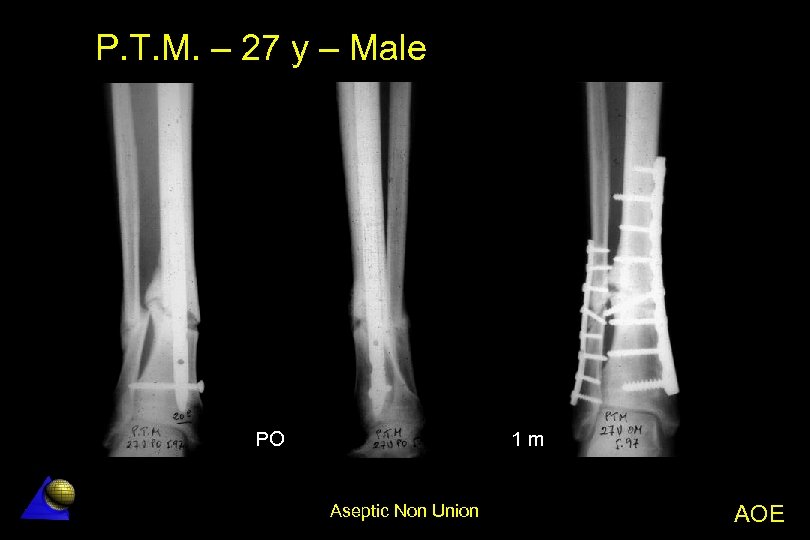

P. T. M. – 27 year old – Male Distal de tibia non-union - 5. 97 l Distal de tibia fx. treated in another Hospital â UTN nailing â Technical defect (only one distal bolt) Non-union with angular deformity l Treatment l â Decortication + Osteotomy â LC-DCP tibia and fibula plate fixation l Excellent result Aseptic Non Union AOE

P. T. M. – 27 y – Male PO 1 m Aseptic Non Union AOE

P. T. M. – 27 y – Male 4 m 24 m Aseptic Non Union AOE